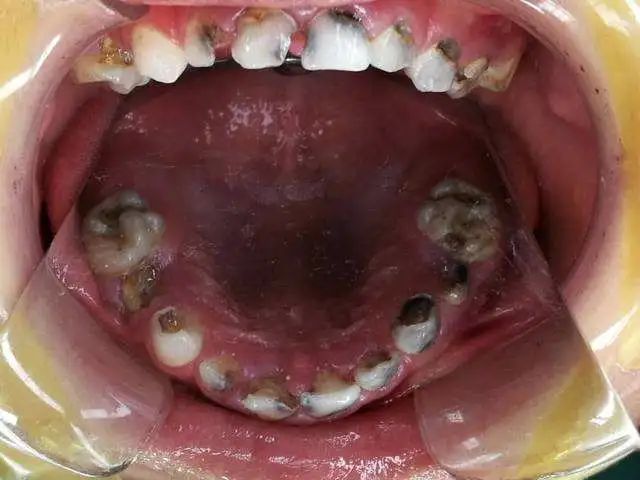

蛀牙是形成“烂牙根”的主要原因,对口腔卫生不重视,容易造成口腔细菌滋生,由刚开始的“小黑点”到形成浅浅的龋洞。若放任不管,牙齿龋坏继续发展,之后牙神经坏死、牙齿变脆、牙体硬组织就会逐渐脱落,慢慢仅剩下残根!这时,再不理不睬,“烂牙根”会引发大问题!

2.残根长期存在会引起根尖炎症:残冠、残根、牙齿髓腔就暴露于口腔的有菌环境之中,细菌可以通过根管而到达根尖,形成根尖周围炎,若不及时处理,可进一步发展成为根尖周肉芽肿甚至根尖囊肿,从而对颌骨形成更大的损害。

3.易嵌塞食物,细菌繁殖影响口腔健康:长时间嵌塞食物,会令残根残冠的位置成为细菌滋生繁殖地,从而形成感染源,容易引发牙龈炎、牙周炎等口腔疾病。